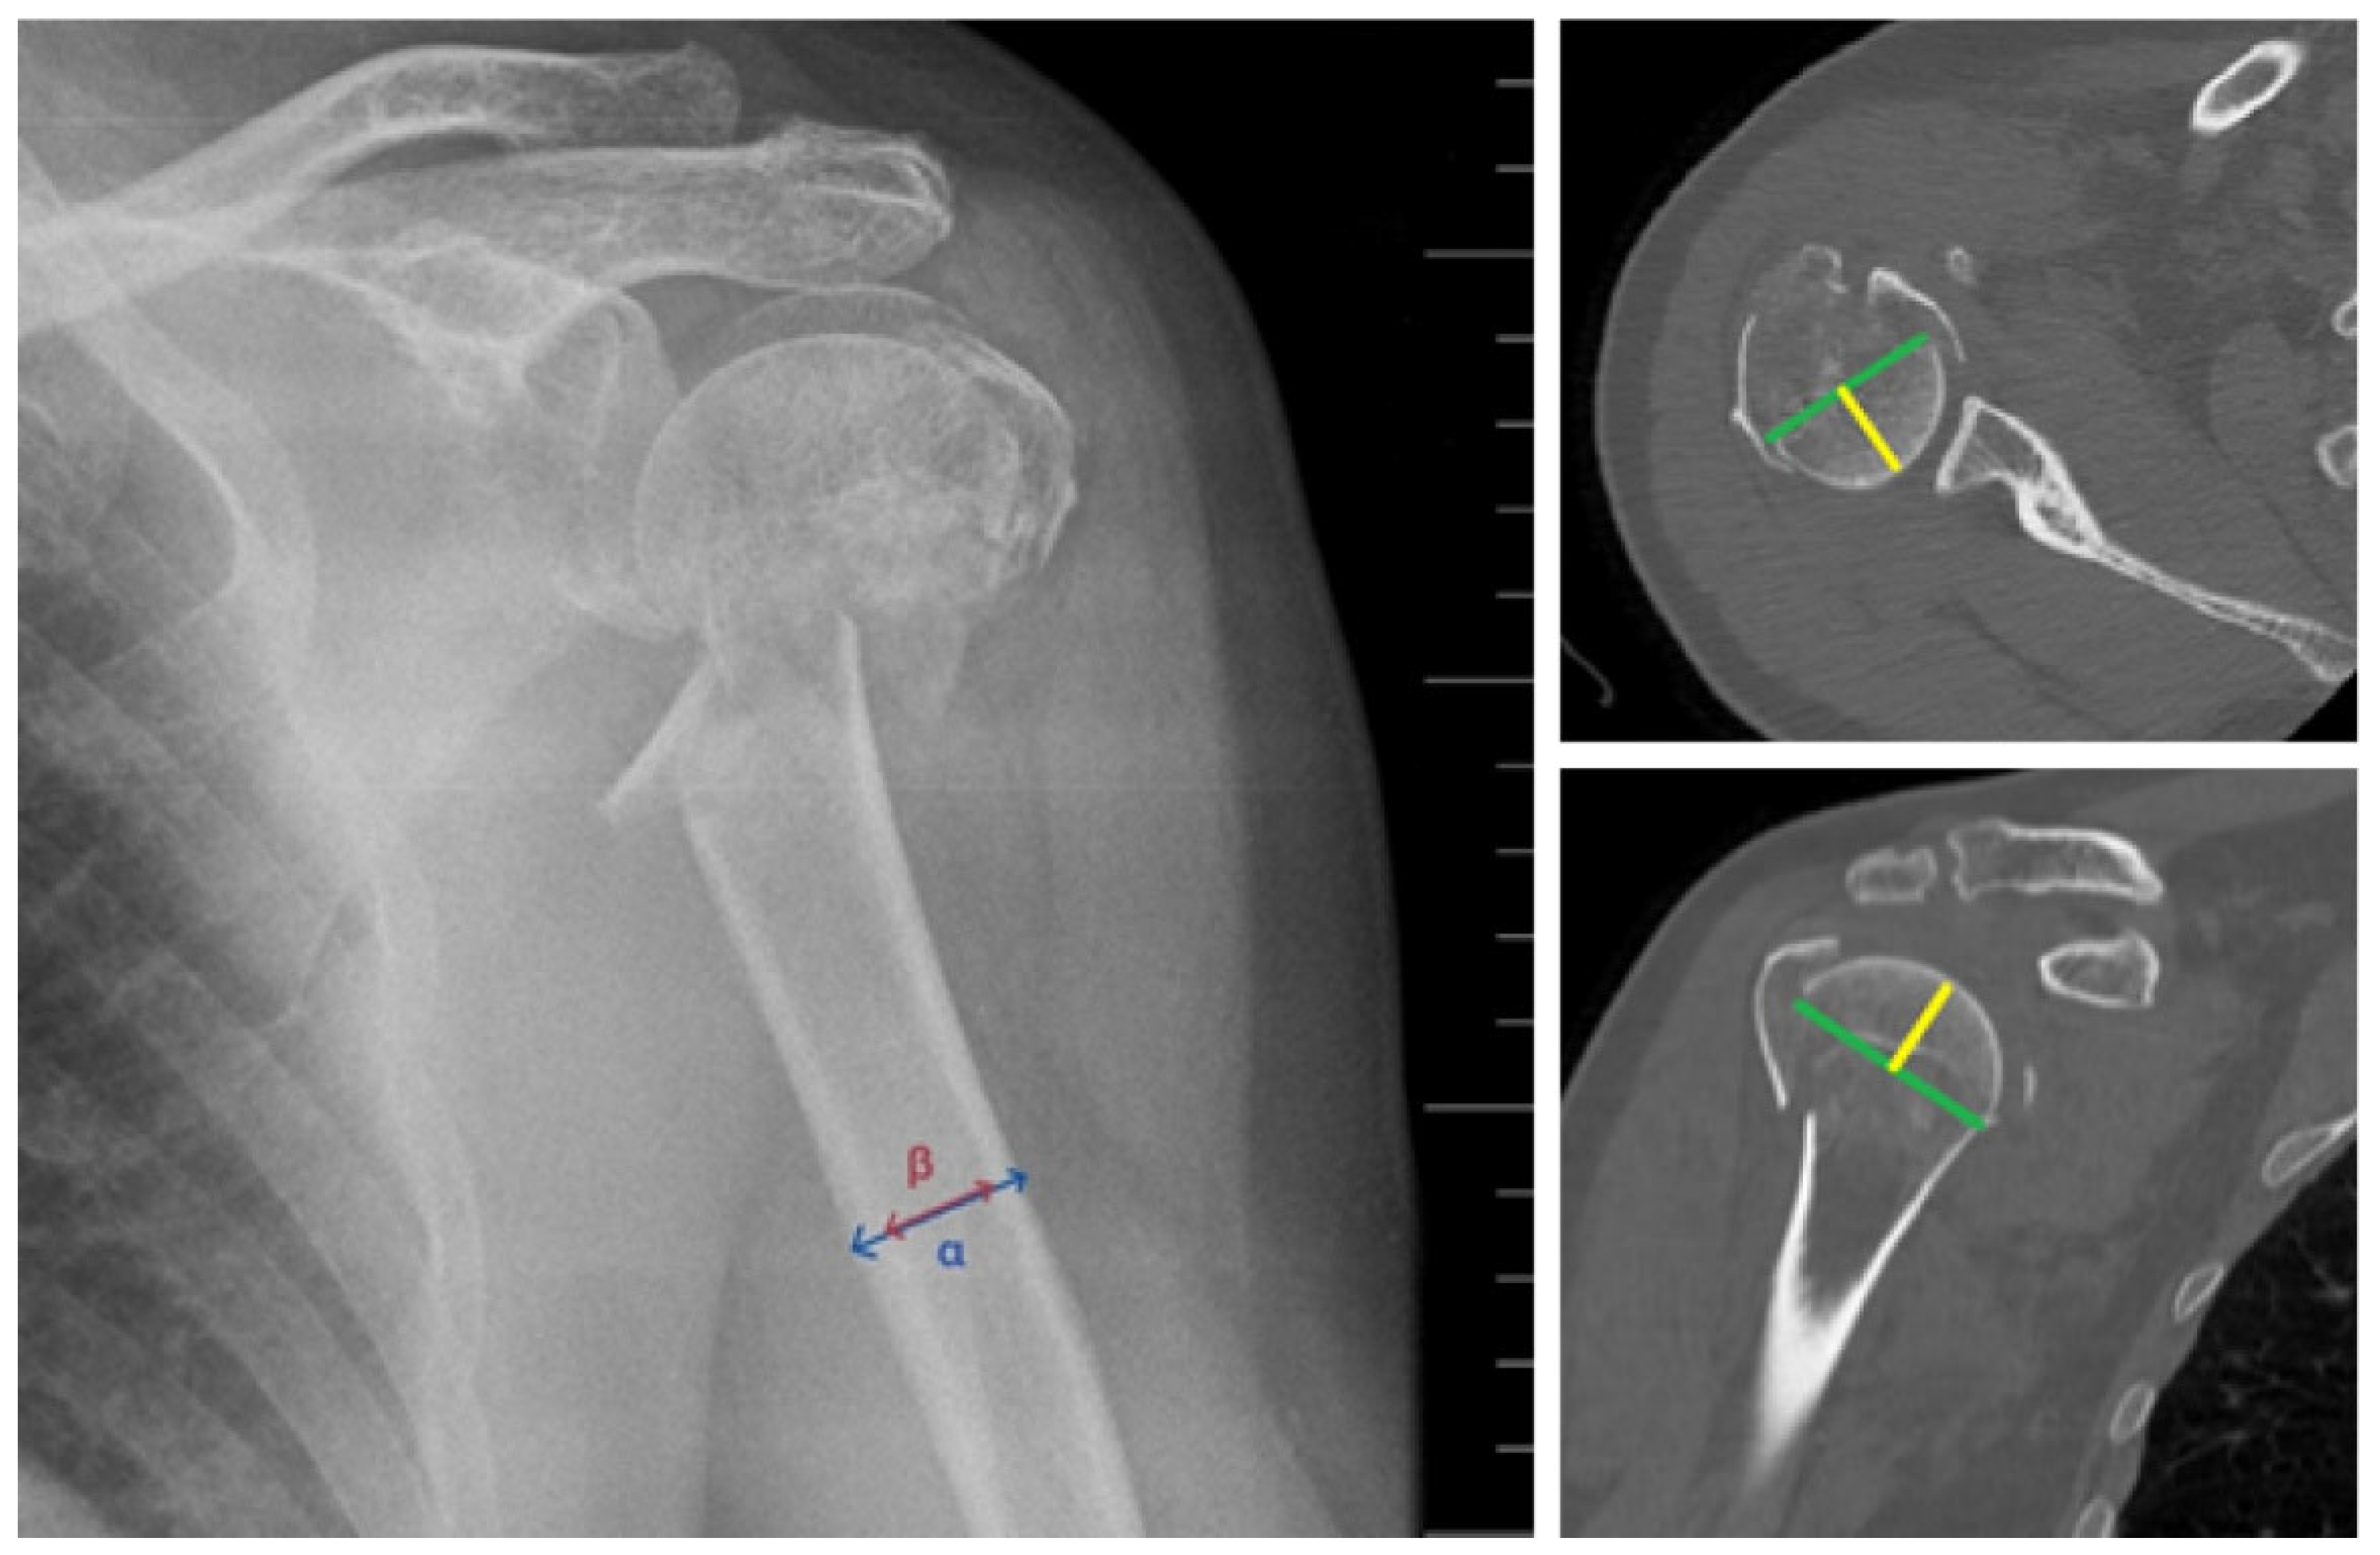

2. Materials and Methods